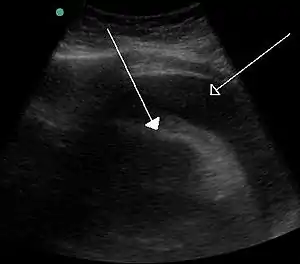

Echocardiogram (ultrasound): when pericardial effusion is suspected, echocardiography usually confirms the diagnosis and allows assessment of the size, location and signs of hemodynamic instability.[5] A transthoracic echocardiogram (TTE) is usually sufficient to evaluate pericardial effusion and it may also help distinguish pericardial effusion from pleural effusion and MI. Most pericardial effusions appear as an anechoic area (black or without an echo) between the visceral and the parietal membrane.[1] Complex or malignant effusions are more heterogeneous in appearance, meaning they may have variations in echo on ultrasound.[4] TTE can also differentiate pericardial effusion based on the size. Although it's difficult to define size classifications because they vary with institutions, most commonly they are as follows: small <10, moderate 10-20, large >20. [4]An echocardiogram is urgently needed for evaluation when there is concern for hemodynamic compromise, a rapidly developing effusion or history of recent cardiac surgery/procedures.[1]